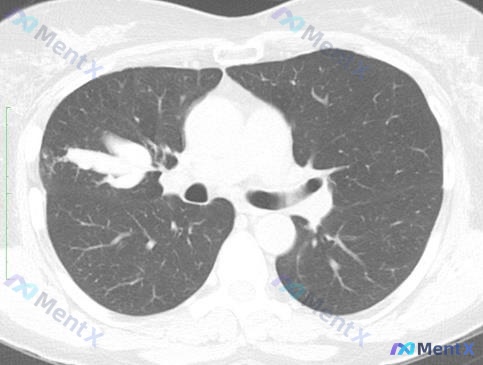

整理了一份很有意思的胸部CT读片病例,常规思路很容易被带偏,分享一下我的分析逻辑。 --- 先看完整影像表现 这份CT的肺窗+纵隔窗给出的信息很明确,也很有迷惑性: 【阳性征象】 1. 右肺门/上叶前段:类结节/团块状实性高密度影,边缘有毛刺,周围轻微纤维条索牵拉胸膜 2. 纵隔窗:病变与周围血管界...